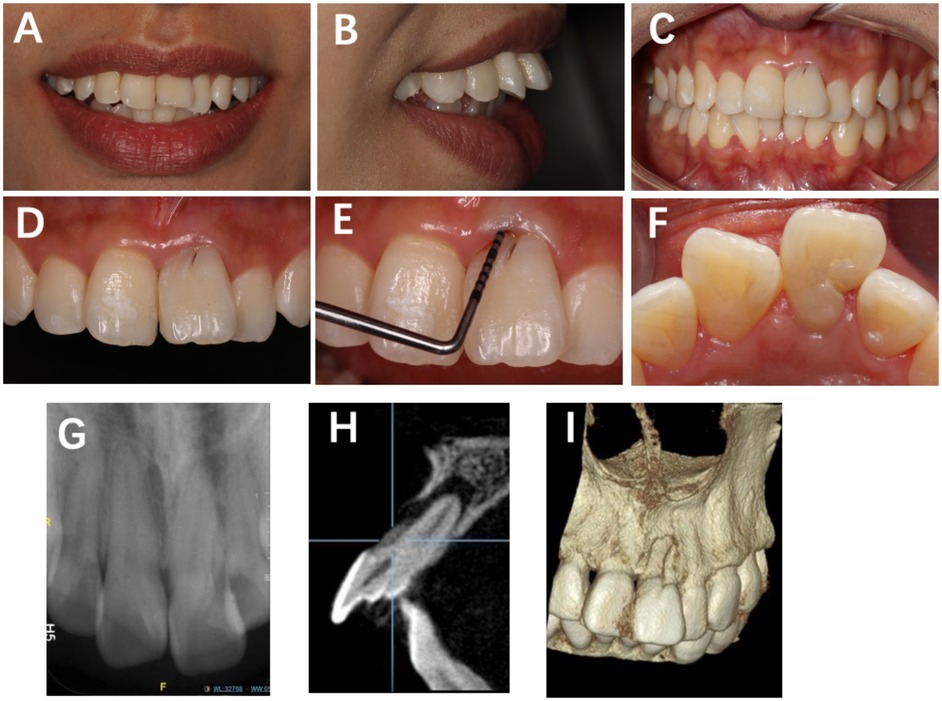

The patient presented with moderate smile line aesthetics, thin gingival tissue with a high scalloped contour, and an acceptable oral hygiene status. A notable deep overbite and overjet were observed in the anterior region. Detailed examination revealed that Tooth #21 exhibited abnormal crown morphology with discoloration, a developmental groove deformity on the labial cervical area with a probing depth (PD) of 10 mm and positive bleeding on probing (BOP), and a developmental groove deformity on the palatal distal cervical area with a PD of 2 mm and negative BOP. Tooth #21 also showed no gingival erythema or swelling and no percussion sensitivity or mobility after testing. Apart from Tooth #21, Teeth #11 and #12 showed smooth, white striated lesions on the labial crown surfaces. A full-mouth periodontal examination noted a mean probing depth of 1.2 mm, and clinical attachment loss was observed only in Tooth #21 (10 mm), with no loss detected in other teeth.

Subsequent periapical radiograph (Dentsply Sirona, Ballaigues, Switzerland) revealed a bifid root canal configuration in Tooth #21 with indistinct morphology, accompanied by a periapical radiolucent area (Figure 1). Cone-beam computed tomography (CBCT) (KaVo Kerr, Brea, CA, USA) 3D reconstruction demonstrated that a developmental groove on the labial root surface of Tooth #21 extends to the apex, with associated labial bone loss. A palatal groove can also be observed (Figure 1F).

A series of images showing dental evaluations: A and B are frontal and side views of a patient's smile. C is an open-mouth view showing teeth alignment. D, E, and F depict close-ups of the gums and teeth with a dental probe in E. G is a dental X-ray image showing roots and alignment. H shows a cross-sectional dental scan. I is a 3D reconstruction of the lower jaw and teeth.

Figure 1. Preoperative clinical view of Tooth #21 showing a distinct labial developmental groove extending from the cingulum toward the gingival margin, accompanied by localized periodontal pocketing. (A) Frontal smile view; (B) lateral smile view; (C) frontal view in centric occlusion; (D) labial surface of Tooth #21 showing a developmental groove; (E) probing depth of 10 mm at the mid-labial site; (F) shallow depression (2 mm) on the distolingual marginal ridge; (G) periapical radiograph showing two root canals, one poorly visualized; (H) periapical radiolucency surrounding the root apex; (I) CBCT 3D reconstruction demonstrating a labial groove along the root surface.